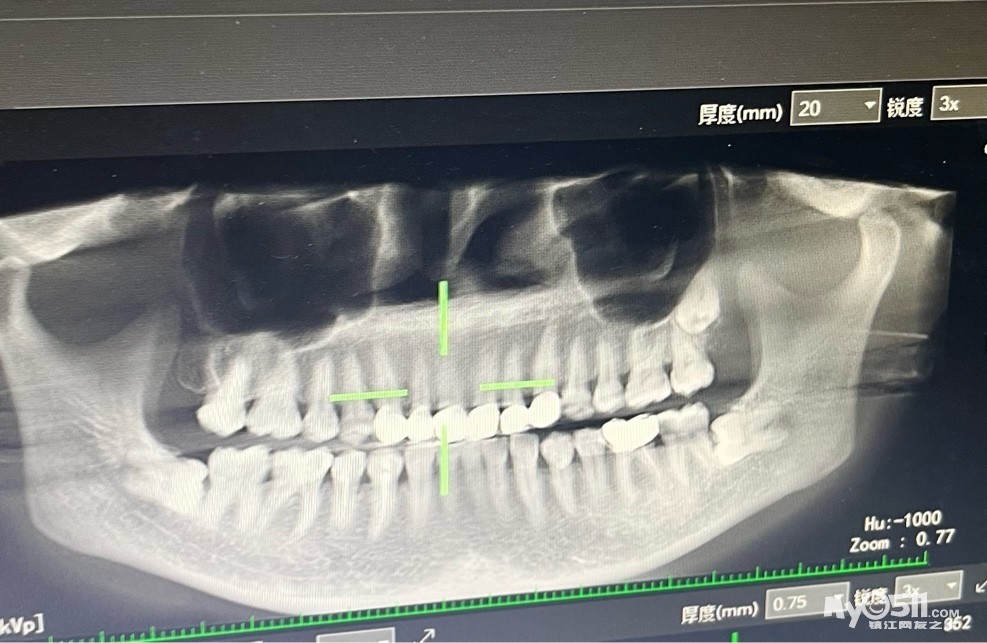

把全埋伏横着长的阻生智齿哪个医院的医生技术好

如题,麻烦大家介绍下,谢谢